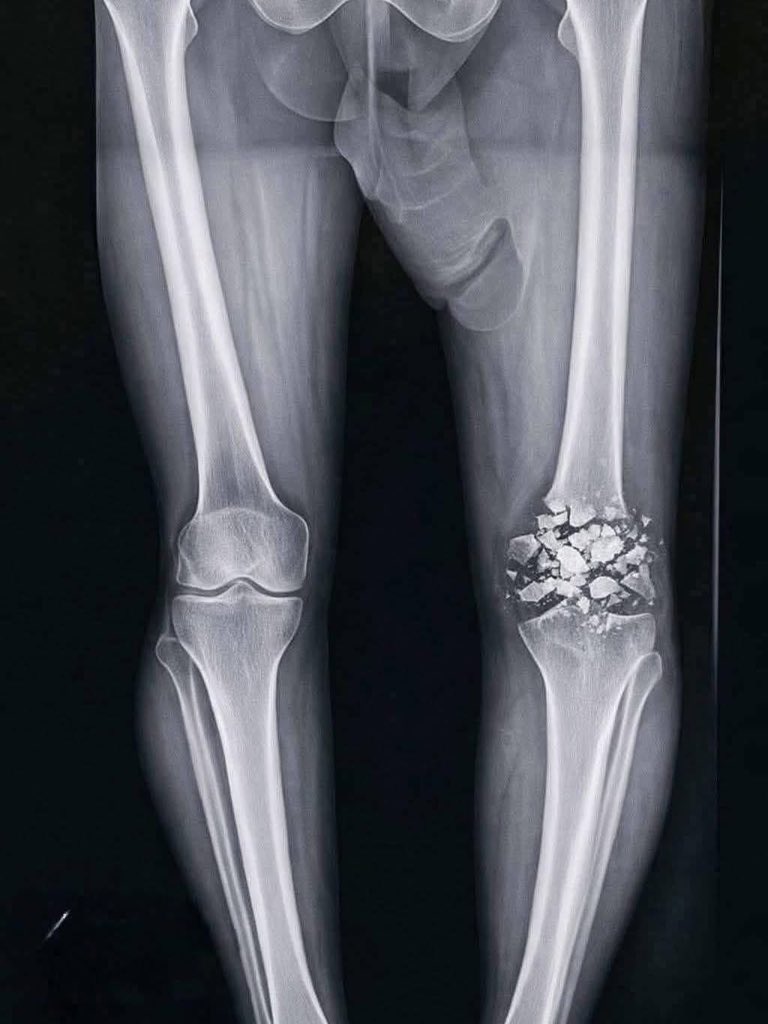

@_xankax @cherrytswizzle vida ya da platin falan takılacak kaynaması bir altı ayı bulur sonrası fizik tedavi vs ortalama bir yıl diyebiliriz

@cherrytswizzle kanka bu net parçalı fraktür, kemik ‘multi- piece edition’ olmuş, geçmiş olsun ama ortopedi bunu bir 6 aya toplar